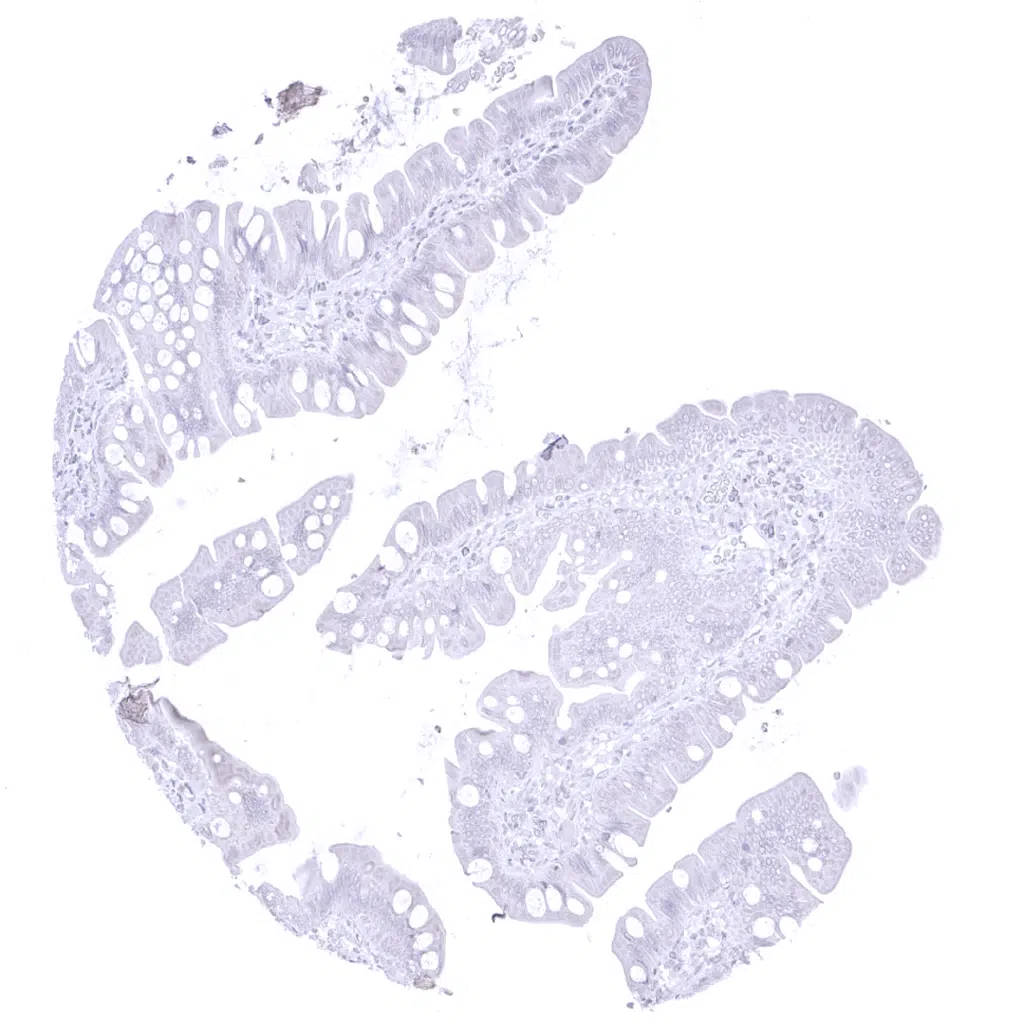

Appendix, mucosa